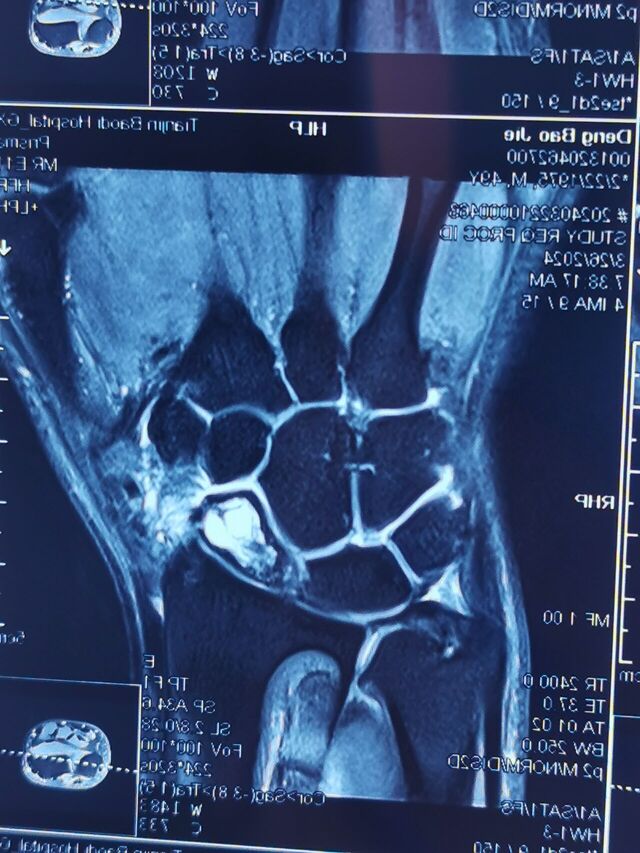

腕关节骨性关节炎

SLAC分期:

I期,舟骨窝局限性关节炎始于桡骨茎突

II期,发展到近端舟骨窝

III期,进而出现头月关节炎

IV期,全腕关节炎

该病例需要做CT重建

判断腕关节骨性关节炎分期

根据分期决定具体术式